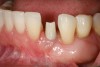

Figure 6  Mucogingival and residual defect after removal of implant in site No. 22.

Figure 6

The patient had no medical concerns and had a history of an implant placement in December 2002 when she was 25 years old. In February 2005, she presented with a mobile implant and an associated advanced peri-implantitis. Radiographic review at the initial examination demonstrated significant destruction of the dentoalveolar ridge around the implant as well as around the adjacent natural dentition. Emergency-based treatment involved surgical implant removal only and debridement of the infection (Figure 4 and Figure 5). Following uneventful healing, an advanced ridge defect was apparent at the edentulous site and moderate and advanced attachment loss noted at No. 22D and No. 21M, respectively (Figure 6 and Figure 7). This case demonstrates bone loss of two separate origins: lack of bone because of tooth agenesis and destruction of bone from inflammatory peri-implantitis.